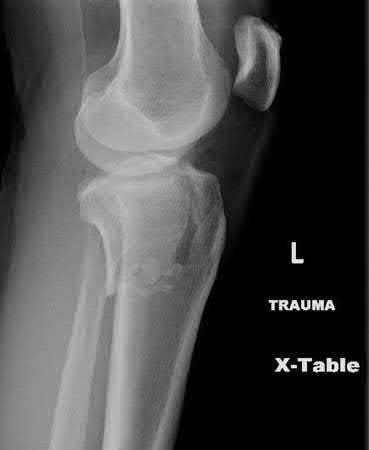

Figure B demonstrates an isolated medial femoral condyle fracture. Lateral locked plating is not an appropriate technique for this fracture.

The fracture shown in Figure B is an AO B type (partial articular fracture). This fracture is best treated with open reduction internal fixation through a medial approach, with lag screw and buttress plate fixation.

Figures A, C, D and E show supracondylar distal femur fractures that can be treated with ORIF with a fixed-angle device such as lateral locked plating.